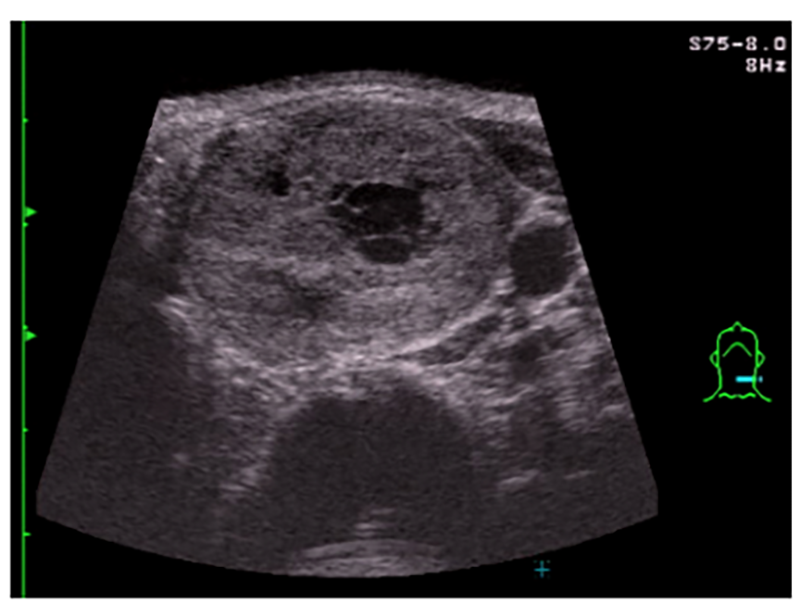

甲状腺エコー検査の一例

当院では、超音波検査、血液検査で甲状腺のがんなどの異常を調べます。